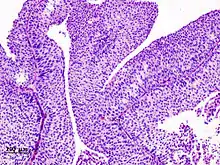

The 1973 WHO grading system for transitional cell carcinomas (papilloma, G1, G2 or G3) is most commonly used despite being superseded by the 2004 WHO[14] grading for papillary types (papillary neoplasm of low malignant potential [PNLMP], low grade, and high grade papillary carcinoma). High-grade carcinoma typically displays more pleomorphism, multiple mitoses, euchromatin and relatively prominent nucleoli, and uneven distribution of nuclei.

Transitional cell carcinoma, being low-grade to the left, and high-grade to the right. H&E stain

Papillary transitional cell carcinoma, low grade

Histopathology of urothelial carcinoma of the urinary bladder, showing a nested pattern of invasion. Transurethral biopsy. H&E stain